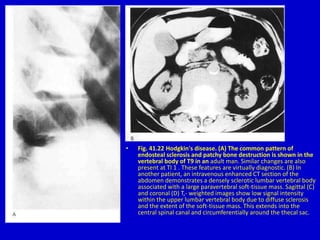

• Fig. 41.22 Hodgkin's disease. (A) The common pattern of

endosteal sclerosis and patchy bone destruction is shown in the

vertebral body of T9 in an adult man. Similar changes are also

present at TI 1 . These features are virtually diagnostic. (B) In

another patient, an intravenous enhanced CT section of the

abdomen demonstrates a densely sclerotic lumbar vertebral body

associated with a large paravertebral soft-tissue mass. Sagittal (C)

and coronal (D) T,- weighted images show low signal intensity

within the upper lumbar vertebral body due to diffuse sclerosis

and the extent of the soft-tissue mass. This extends into the

central spinal canal and circumferentially around the thecal sac.